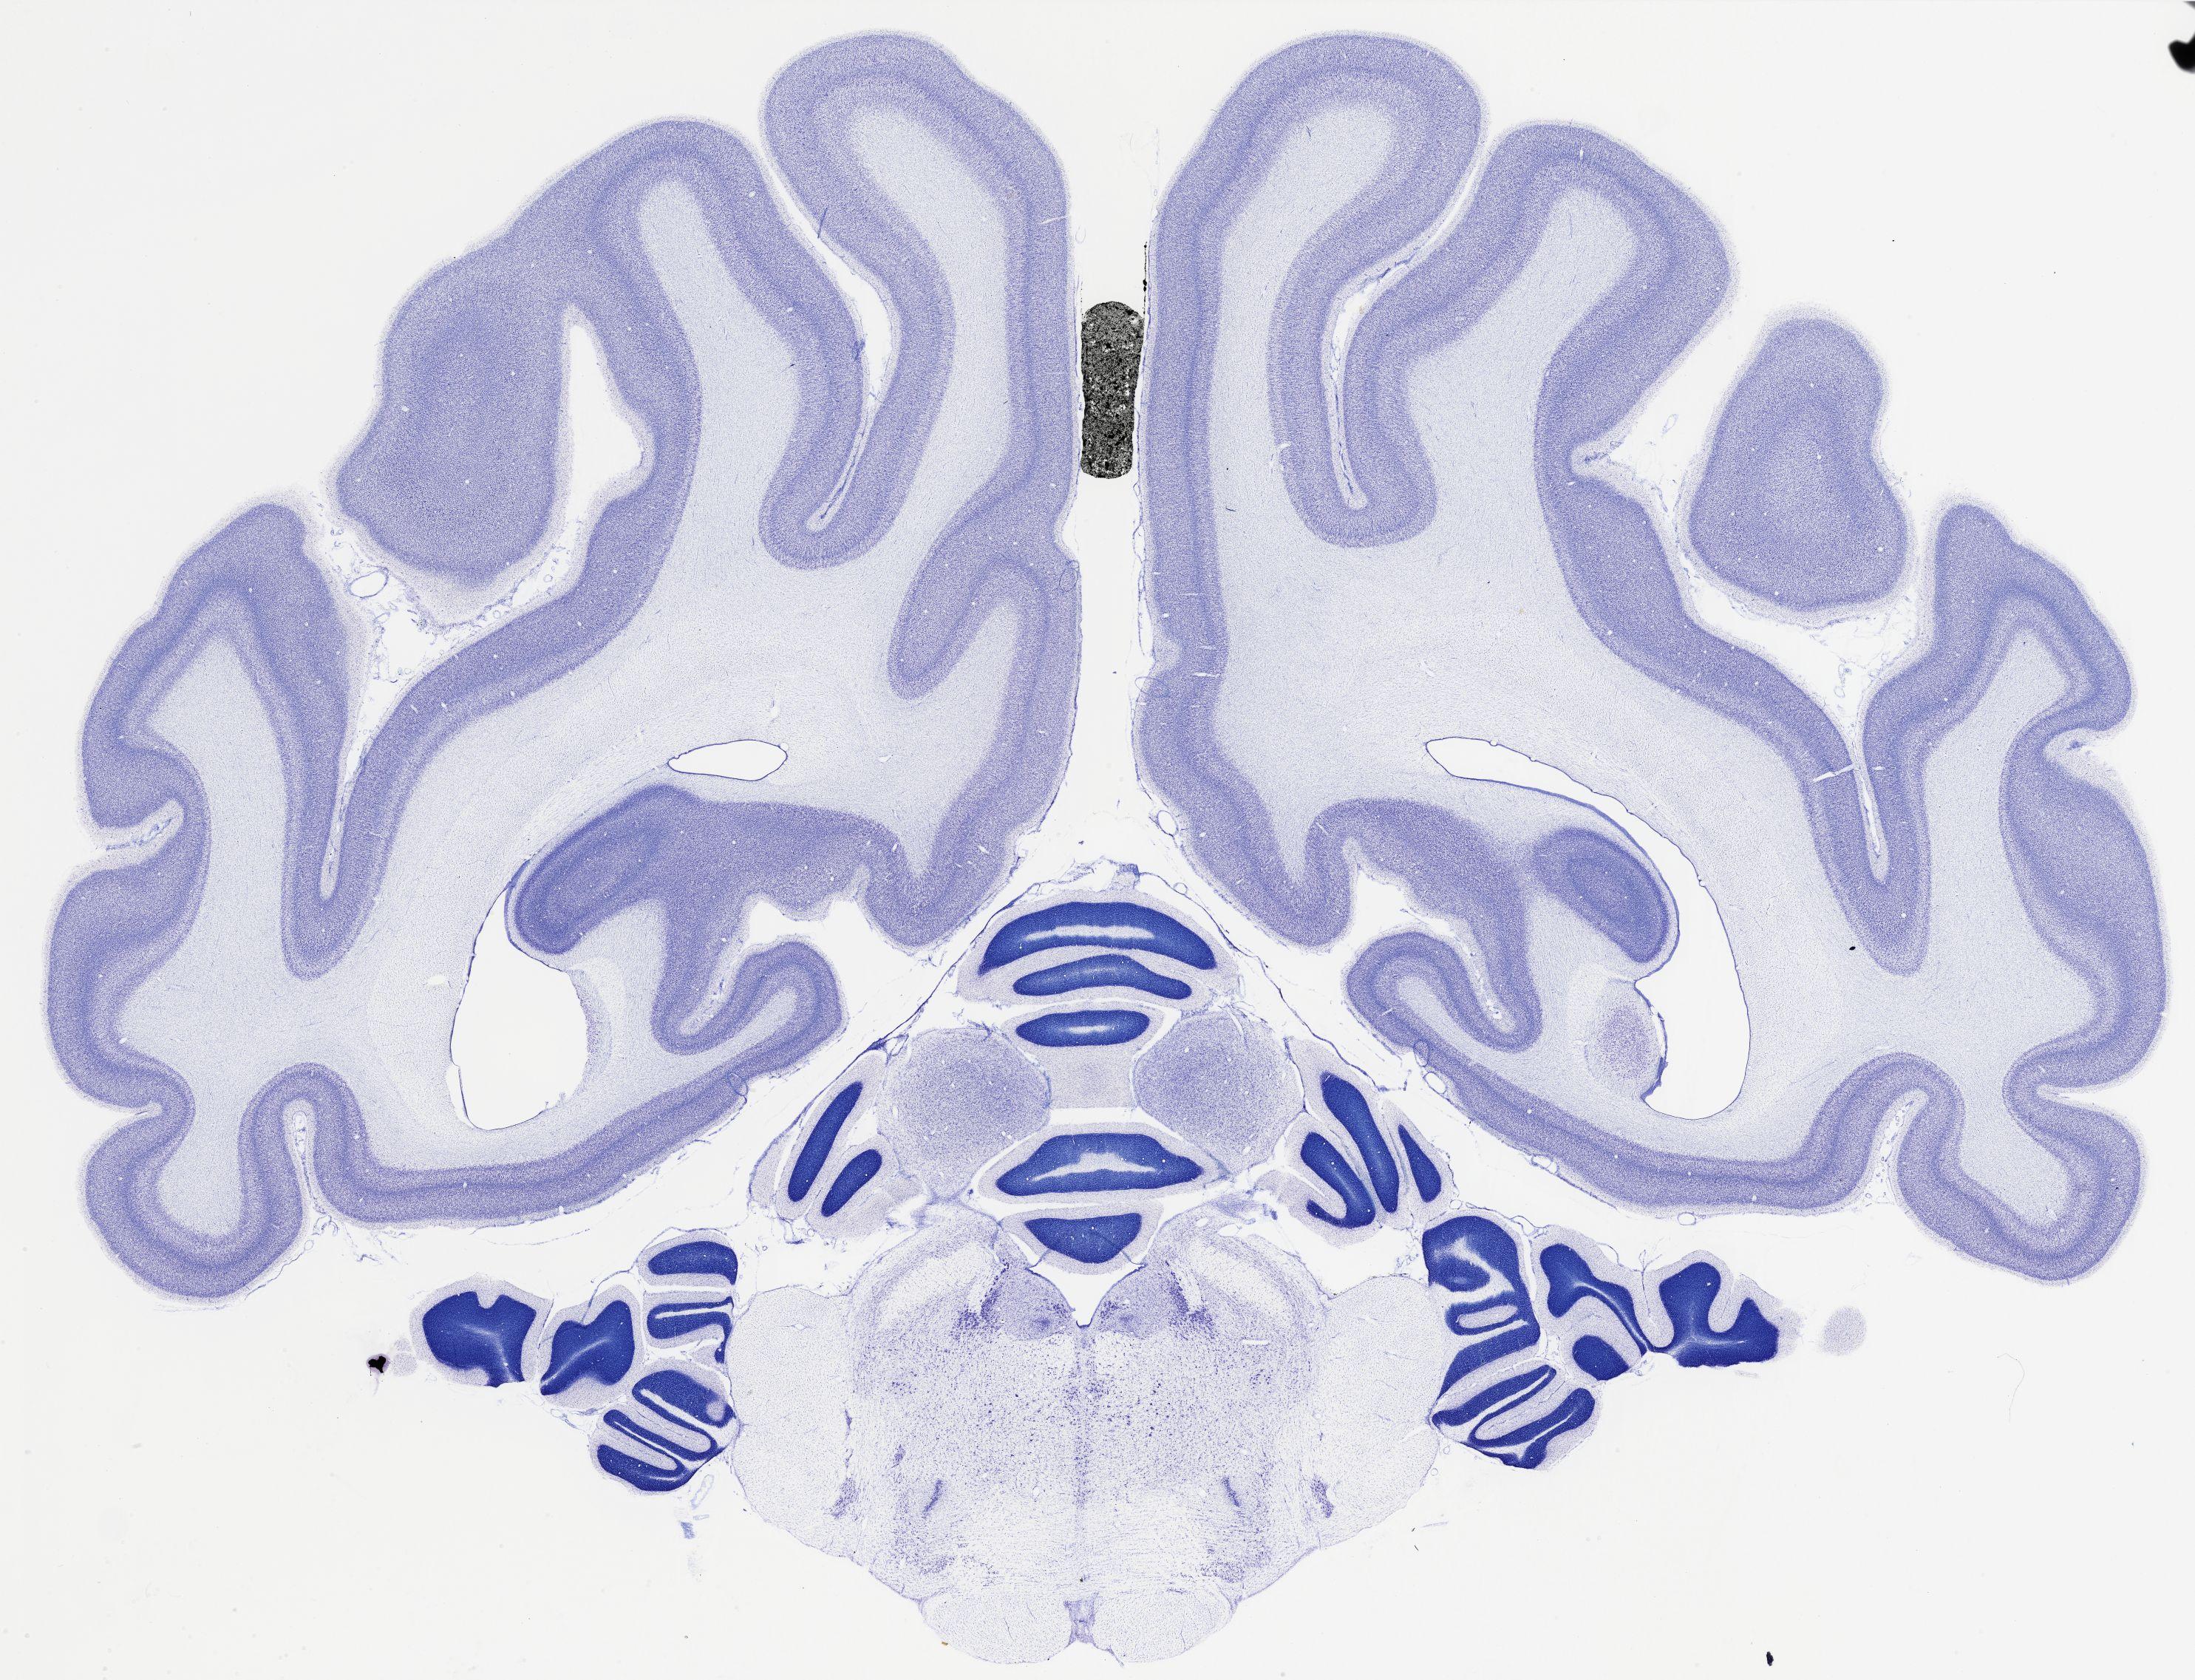

Datasets -> Chlorocebus Aethiops -> Nissl, coronal, histo, Whole-Brain, adult

[ Metadata ]   ·   Source: NeuroScience Associates

Displaying Sections 481 thru 520 of 740 Sections for this Dataset

thumbnail

524